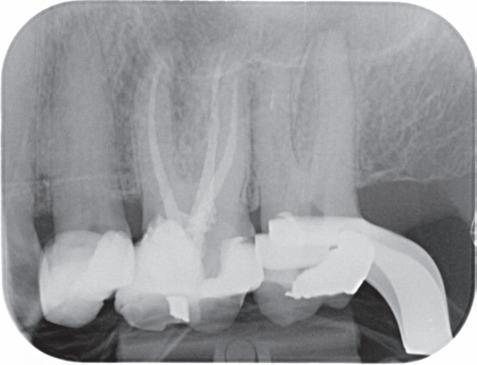

Voordat je aan een wortelkanaalbehandeling begint, zorg je voor (of maak je) een goede beginfoto waar het te behandelen gebitselement volledig op staat afgebeeld. Deze foto geeft essentiële informatie: de grootte van de pulpakamer en de ligging ervan; het aantal en de vorm van de wortels en de breedte van hun wortelkanalen en de lengte van de wortels. Hiermee kan je de DETI-score bepalen en de moeilijkheidsgraad inschatten. De grootte en de ligging van de pulpakamer op de röntgenfoto in combinatie met de ideale anatomische vorm, zoals in foto 1 is aangegeven, bepaalt de uiteindelijke vormgeving van de opening. Bij de molaren liggen de kanaalingangen in de buurt van de knobbeltoppen. Als die niet meer in originele staat

(kroon, restauratie) zijn, kan je ook de wortel gebruiken. Soms moet je net subgingivaal sonderen, maar de kanaalingang ligt in het middel van de wortel. Als je die plek visualiseert en projecteert op je opening, boor je de goede kant op. Nog een tip: wees bij het openen niet spaarzaam met het wegnemen van aanwezig restauratiemateriaal (wees wél spaarzaam met het onnodig wegnemen van tandweefsel).

2. Het afgebroken instrument op de foto van de verwijzend tandarts.

3. De opening is vrij klein gekozen. In rood is de ideale opening aangegeven, de tandarts had veel meer restauratiemateriaal mogen wegnemen.